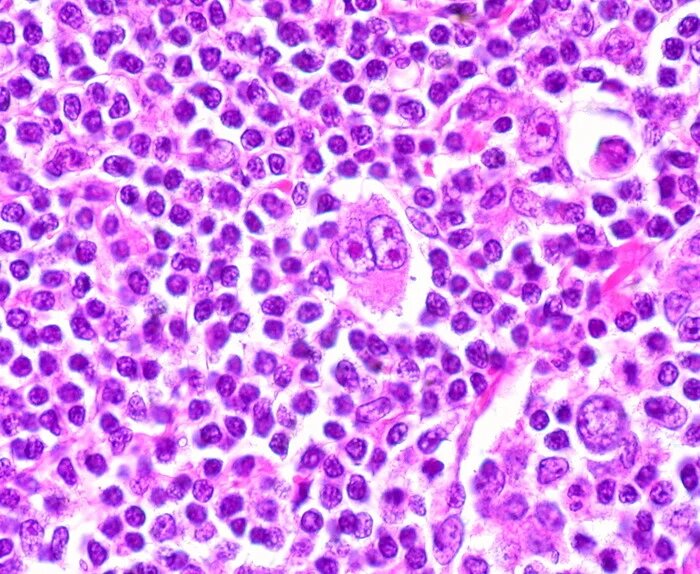

• Особенности: Для этого типа характерно наличие специфических клеток Рид-Березовского-Штернберга. Часто поражает лимфоузлы средостения, вызывая их значительное увеличение.

Клетки Березовского-Рид-Штернберга